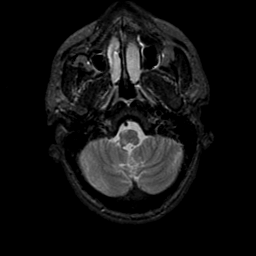

MR Study #9, April 14, 1991 -- Slice #7

[Home][Help][Clinical][Tour 1][Tour 2] Slice 7